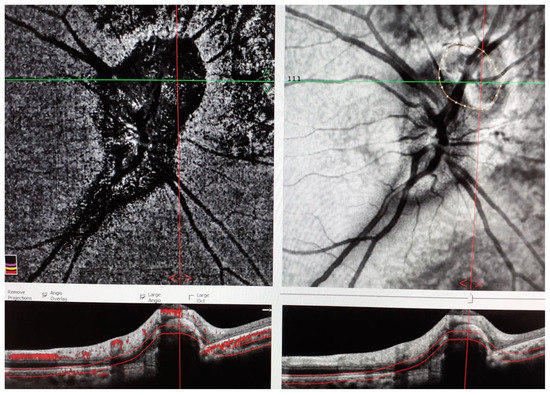

Juxtapapillary Choroidal Neovascularization in a Young Woman with Tubulointerstitial Nephritis and Uveitis (TINU) Syndrome with Onset in Pediatric Age

2. Case Presentation